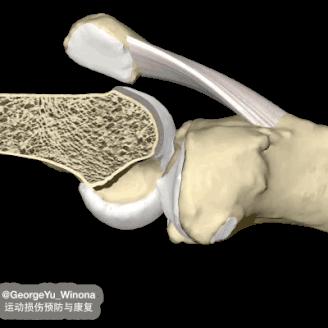

股骨、胫骨和髌骨共同构成膝关节的骨性结构,在互相接触的关节面,都覆盖一层光滑的关节软骨,同时股骨和胫骨之间有半月板,关节腔内有关节液。

三者相互配合润滑关节、减少摩擦,在运动中缓冲压力,共同维护关节的正常功能和状态。